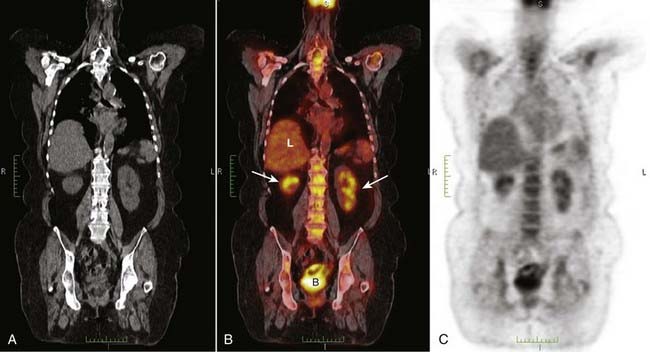

image By fusing the PET and CT images, the anatomical location of the functional abnormality is determined (Fig. 27).

image

Figure 27 PET/CT fusion image.

By fusing the PET and CT images, the anatomical location of the functional abnormality can be determined. The CT scan (A) is superimposed on the PET image (C) to form the PET/CT fusion image (B). Uptake of FDG is depicted by varying intensities of red. Normal uptake is seen in the liver (L) and normal excretion is through the kidneys (white arrows) into the bladder (B). The more concentrated the uptake, the more intense the red color.